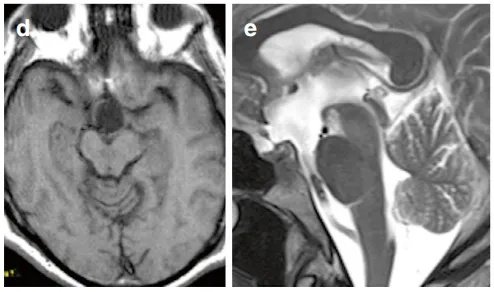

術(shù)后MRI證實(shí)腫瘤已肉眼全切(圖d、e)。

術(shù)后MRI證實(shí)腫瘤已肉眼全切

手術(shù)未出現(xiàn)并發(fā)癥,術(shù)后亦未見新發(fā)神經(jīng)功能、認(rèn)知或內(nèi)分泌障礙。術(shù)后的局部美容效果良好,術(shù)后12天照片所示手術(shù)瘢痕已較為滿意(圖f)。